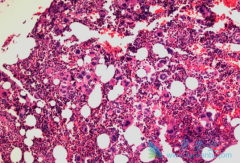

肝细胞癌 (HCC)是世界上最常见和最致命的癌症之一,特别是在东亚和南非等国家。肺是晚期肝癌最常见的肝外转移部位之一,预后极差,目前索拉非尼是其标准的一线治疗选择。然而一线治疗进展后,HCC肺转移可用的药物非常有限,急需研发新的药物和治疗方 ...